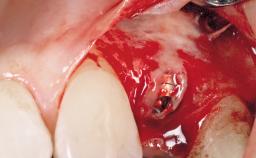

Surgical treatment of a 67-year-old male patient exhibiting an extended edentulous space in the anterior maxilla after the removal of three hopeless incisor teeth.

The video demonstrates implant placement using a surgical stent according to the principle of prosthodontically driven implant placement. The deficient ridge is augmented with locally harvested autologous bone chips, a superficial layer of xenogenic DBBM particles and a resorbable collagen membrane. The surgery is completed with a precise, tension-free primary wound closure.